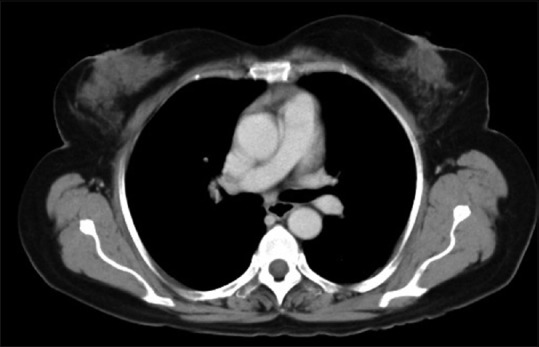

A 65-year-old female with no history of comorbidities was admitted to our hospital on July 5, 2014 with painless lump in her right breast. On detailed history taking, patient had no history of fever, night sweats, or weight loss (B symptoms). Physical examination revealed a hard, nontender, mobile mass of approximately 6 cm × 7 cm occupying all quadrants of the right breast. The contralateral breast was normal. On physical examination, patient had no evidence of cervical, axillary or inguinal lymphadenopathy. Liver and spleen were not palpable. The laboratory tests revealed the following: Hemoglobin of 11.9 g/dl, total leukocyte counts of 10,400/mm3, platelet counts of 48,600/mm3, serum creatinine of 0.72 mg/dl, alkaline phosphatase of 55 IU/L, serum glutamic pyruvic transaminase of 22 IU/L, serum glutamic oxaloacetic transaminase of 13 IU/L, total bilirubin levels of 0.88 mg/dl, serum albumin of 4.34 g/dl, lactate dehydrogenase (LDH) of 172 U/L, and serum uric acid of 4.52 mg/dl. Excisional biopsy performed showed atypical lymphocytic infiltration suspicious of non-Hodgkin's lymphoma (NHL) [Figure 1]. Immunohistochemistry revealed positivity to CD20 [Figure 2], CD79a and MUM1 and negativity to CD2, CD3, CD5, CD10, and AE1. MIB-1 index was 95%. On the basis of histopathologic features, tumor was classified as DLBCL, non-germinal centre B-cell-like (non-GCB DLBCL). Bone marrow aspiration and biopsy were performed and revealed a hypercellular bone marrow with no evidence of lymphomatous infiltration. The cerebrospinal fluid cytological examination was negative for any malignant cells. Computed tomography (CT) of the neck, thorax, abdomen, and pelvis revealed 66 mm × 68 mm × 84 mm large multi-lobulated soft tissue density lesion involving all quadrants of right breast reaching up to the skin [Figure 3]. No systemic lymphadenopathy was detected. The CT findings indicated stage I E of the lymphoma tumor according to the Ann Arbor staging system. The patient received six courses of cyclophosphamide, doxorubicin, vincristine, prednisolone plus rituximab (R-CHOP) chemotherapy. After four courses of R-CHOP, the follow-up chest CT scan showed decreased the size of the right breast mass (6.6 cm × 6.8 cm → 3.4 cm × 1.4 cm) [Figure 4]. After six courses of R-CHOP, the follow-up chest CT scan showed no visible mass in the breast. The patient was put under close observation. At present, after follow-up period of 20 months, the patient is surviving with no evidence of disease and with no morbidities associated with chemotherapy.

| Figure 3:Computed tomography scan showing a large multi-lobulated soft tissue density lesion involving all quadrants of right breast reaching up to the skin measuring 66 mm × 68 mm × 84 mm